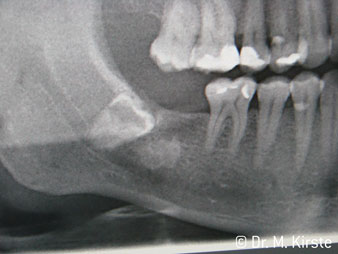

Угол 45° наконечника был выбран специально с учетом широкого круга преимуществ. Коллеги, которые работают в хирургии, и для которых этот наконечник был изначально создан, быстро оценят возможность эффективно работать в очень стесненном пространстве. В частности, при удалении зуба мудрости (рис. 2) не нужно сильно раздвигать мягкие ткани в области щеки (рис. 3). Конструкция головки наконечника в сочетании с небольшим поворотом головки во время препарирования позволяет быстро и безопасно выполнять работу в области задних коренных зубов.

Профессиональная конструкция подшипников внутри головки обеспечивает тихую работу бора; впечатляет атравматичное разделение зуба и корня (рис. 4-9).